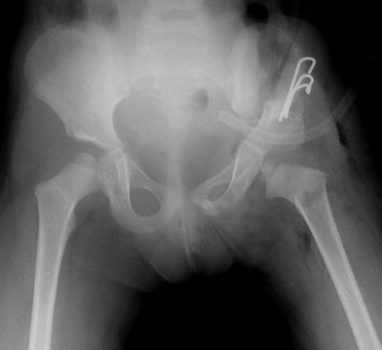

Тройная остеотомия таза

Существует несколько методик тройных ОТ. Каждая из них подразумевает пересечение всех составляющих тазового кольца (лобковой, подвздошной и седалищной костей). После этого вертлужную впадину устанавливают в нужном положении, а костные фрагменты фиксируют титановыми конструкциями. Винты удаляют спустя 1-1,5 года, то есть после того как кости прочно срастутся.

Чаще всего в ортопедии используют несколько техник тройной остеотомии. К ним относится ОТ по Tonnis, Steel, Chiari, ротационная ацетабулярная и ряд модификаций типа Bernese, Ganz, RAO. Все перечисленные методики обеспечивают хорошую мобилизацию вертлужной впадины и позволяют установить ее в наиболее выгодном положении.